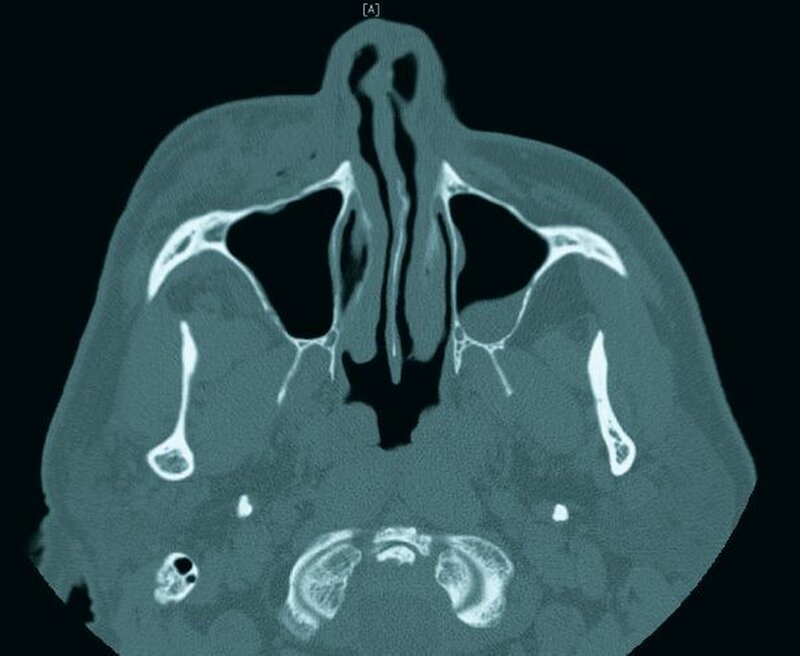

Eine 62-jährige Patientin im Zustand nach endodontischer Behandlung am Zahn 14 stellte sich bei uns in der Uniklinik vor. Bei der Spülung der Wurzelkanäle mit Natriumhypochlorit kam es zur Überpressung von Spülflüssigkeit in das periapikale Gewebe. Nach Abbruch der Behandlung bei einer eintretenden Schwellung im Bereich der Wange wurde die Patienten in die Klinik überwiesen.